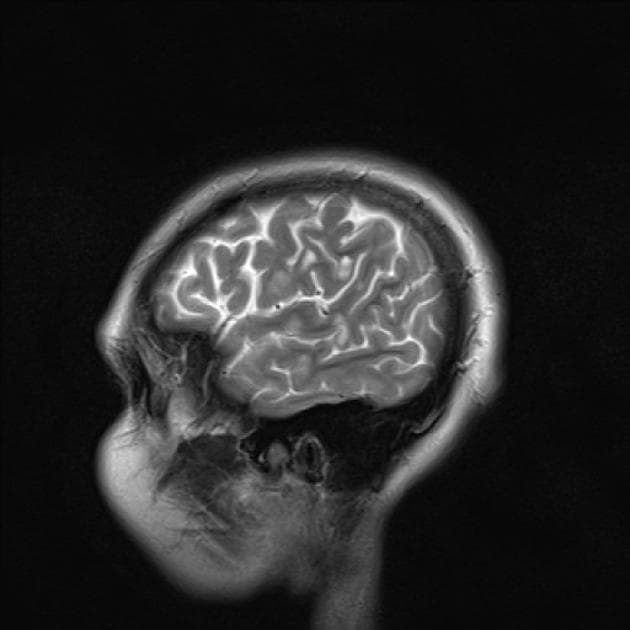

- Hạn chế khuếch tán (restricted diffusion) lan tỏa ở chất trắng vùng trên lều tiểu não, tương ứng với các vùng tăng tín hiệu trên hình ảnh FLAIR.

- Ngoài ra, có các vùng tăng tín hiệu trên FLAIR ở dải vỏ não (cortical ribbon) và các nhân nền (basal ganglia) hai bên, với hạn chế khuếch tán tương ứng nhẹ ở vùng vỏ quanh vận động (peri-rolandic cortex).

Xét theo tiền sử bệnh lý, các phát hiện hình ảnh này phù hợp với bệnh lý thoái hóa trắng sau thiếu oxy chậm (delayed posthypoxic leukoencephalopathy) sau tổn thương não do thiếu oxy-thiếu máu (hypoxic-ischemic encephalopathy).

- "Chụp cộng hưởng từ cho thấy hạn chế khuếch tán lan tỏa ở chất trắng và tăng tín hiệu trên FLAIR, thường kèm theo tổn thương ở vỏ não và nhân nền."